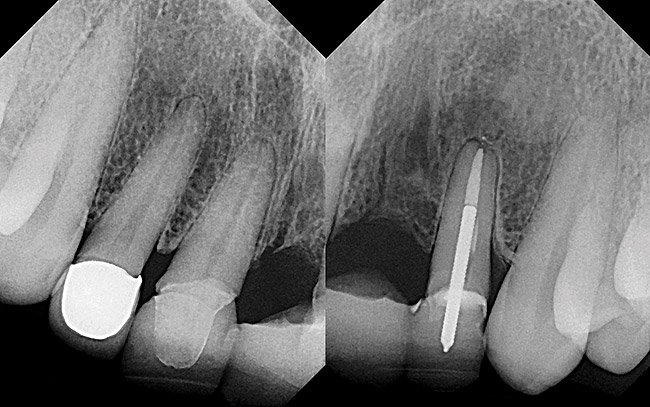

Figure 12  (Case 2) Initial radiograph of compromised implant No. 7.

Figure 12

Figure 13  (Case 2) Clinical presentation of No. 7 implant. Note discrepancy in crown length due to bruxism.

Figure 13

A 53-year-old woman presented with a failing implant in the No. 7 site (Figure 12 and Figure 13). Her desire was to eliminate infection and preserve esthetics. A team effort between the periodontist and restorative dentist to advocate for additional restorative dentistry as well as manage the patient’s expectation of time required was essential. In addition, the patient needed to have realistic expectations of a compromised outcome. Both the restorative dentist and the periodontist informed the patient about the difficulty of achieving this with acceptable esthetic results. Mutual emotional and technical support was required to successfully complete this case, from initial grafting of the defect to placement of anterior restorations (Figure 14 through Figure 23).